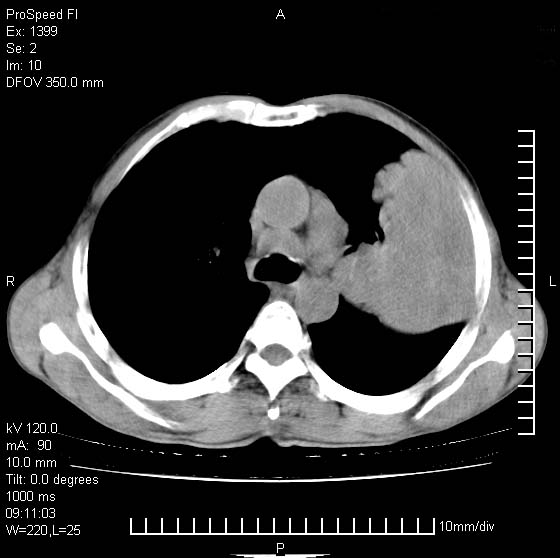

以下是引用rgsyyf在2007-1-19 11:05:00的发言:[br]左肺上叶见形态不规则巨大软组织肿块影,边缘呈分叶征,纵隔内隆突下见肿大淋巴结,右肺内另见一不规则结节影 .考虑:左肺周围性肺癌伴纵隔即右肺内转移.